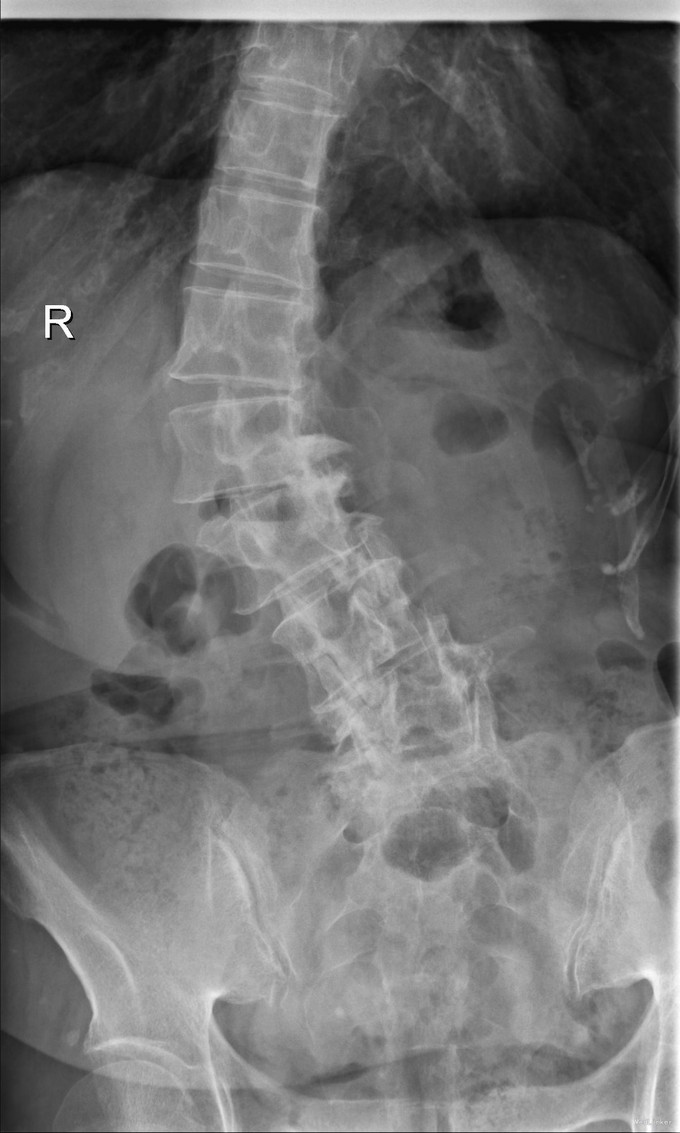

主诉:右下肢麻木11年,腰部酸痛无力 现病史:女性患者,65岁,患者于11年前无明显诱因下出现右下肢麻木,自大腿至右踝部,站立位加重。未予重视,后期出现腰臀部僵硬,弓背僵硬无力,自主行走距离不足200米,曾于06年经X线平片及MRI检查:腰椎椎管狭窄伴有腰椎滑脱,椎间盘突出等。

查体:侧弯畸形,右臀部及右下肢麻木疼痛,腰部活动受限,难以站立。右侧支腿抬高试验60°。双下肢肌力肌张力可。 辅助检查:平片:腰椎侧弯,椎体滑脱,曲度后凸 磁共振:L2-3,L4-5,L5-S1腰椎椎管狭窄,l2-3L3-4L4-5L5-S1腰椎间盘突出,腰椎退变

诊断: 腰椎侧弯,腰椎间盘突出 治疗:1期微创侧路椎体融合术+2期 微创后路经皮内固定术